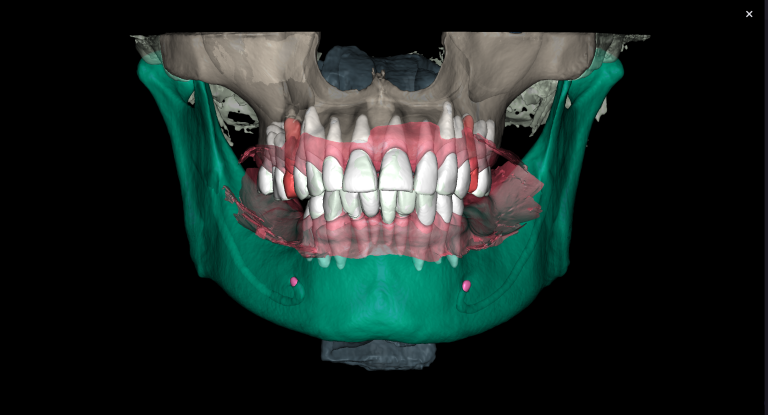

3D reconstruction created on the basis of DICOM and an intraoral scan in the Diagnocat STL module allows you to choose the optimal size and location of the implants

A template for guided implant surgery was planned and manufactured based on these digital models for the replacement of teeth 24 (Universal 12) and 25 (Universal 13)

The result of collaboration with Diagnocat AI is a favorable outcome of the orthodontic and surgical stages of treatment